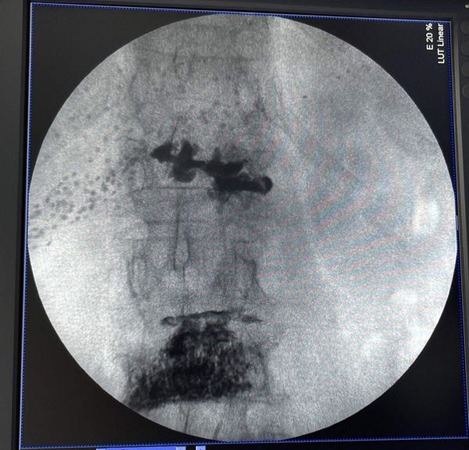

Відтепер в КМП «Лікарня Придніпровська» проводять сучасні малоінвазивні оперативні втручання при ураженнях хребтового стовпа. Пункційна вертебропластика – це малоінвазивна хірургічна процедура, яку застосовується при компресійних переломах хребців, що виникають внаслідок остеопорозу. Суть методики полягає в тому, що під місцевим знеболюванням хворому вводять спеціальну голку в ушкоджений хребець та здійснюють введення спеціального кісткового цементу. Він затвердіває та відновлює щільність хребця, за рахунок чого значно зменшується больовий синдром.

Представляємо клінічний випадок хворої 70 років з компресійними переломами хребців L1 та L3, яка надійшла у відділення хірургії зі скаргами на виражений біль у хребті та неможливість самостійно пересуватися. Пацієнтці проведено пункційну вертебропластику. Наступного дня хвора виписана з лікарні зі значним зменшенням больового синдрому і почала самостійно ходити.